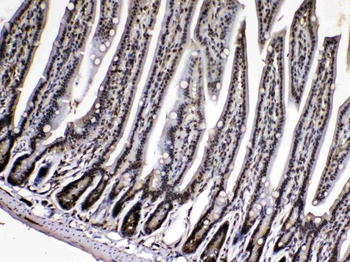

Anti-Cyclophilin A/PPIA Antibody [orb19174]

FC, ICC, IF, IHC, IHC-Fr, WB

Human, Mouse, Rat

Rabbit

Polyclonal

Unconjugated

10 μg, 100 μgCYPA Rabbit Polyclonal Antibody [orb100498]